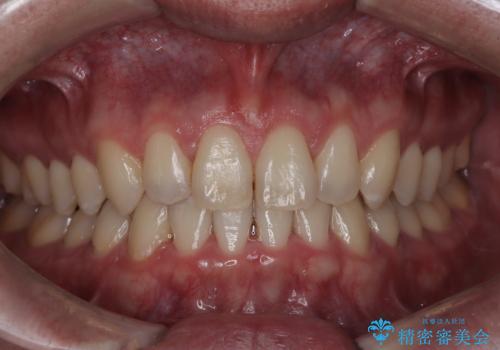

【インビザライン】前歯のねじれを治したい。

- 前歯の凸凹を主訴に来院されました。

スペースを作るために顎間ゴムを使用して、奥歯の遠心移動をおこない配列しました。

奥歯の遠心移動を行うことで、犬歯関係も良い状態に仕上げることができました。